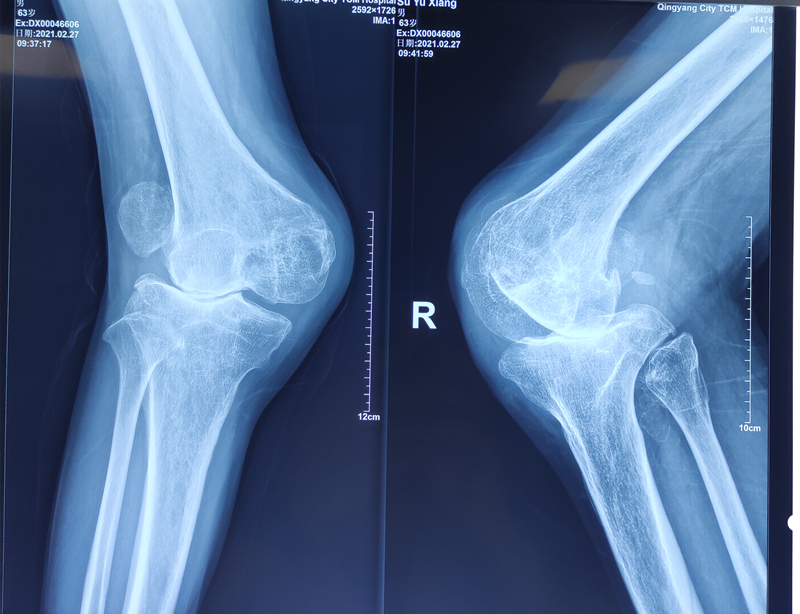

骨二科成功完成一例高難度人工膝關(guān)節(jié)置換術(shù)

我院骨傷二科李崇鑫副主任醫(yī)師成功完成一例雙側(cè)膝關(guān)節(jié)重度外翻人工膝關(guān)節(jié)置換術(shù)。

患者蘇某,男,63歲,17歲時(shí)雙膝關(guān)節(jié)被土方塌傷,當(dāng)時(shí)由于條件有限,未及時(shí)治療。現(xiàn)如今畸形嚴(yán)重,必須依靠雙拐支撐走路,并且呈逐漸加重趨勢(shì),多處求醫(yī)無果。經(jīng)打聽,找到我院骨二科李崇鑫副主任醫(yī)師。

入院診斷為雙側(cè)膝關(guān)節(jié)外翻畸形(重度),雙側(cè)髕骨陳舊性脫位,雙側(cè)膝關(guān)節(jié)屈曲攣縮畸形。由于患者年齡偏大,病情嚴(yán)重,手術(shù)技術(shù)要求高,難度及風(fēng)險(xiǎn)極大,一旦失誤,將會(huì)帶來災(zāi)難性的后果。李崇鑫副主任醫(yī)師積極準(zhǔn)備手術(shù),詳細(xì)制訂手術(shù)方案,于3月16日下午順利完成右側(cè)人工膝關(guān)節(jié)置換手術(shù)。術(shù)程順利,術(shù)后外翻畸形完全糾正,恢復(fù)正常力線,髕骨軌跡完全糾正。